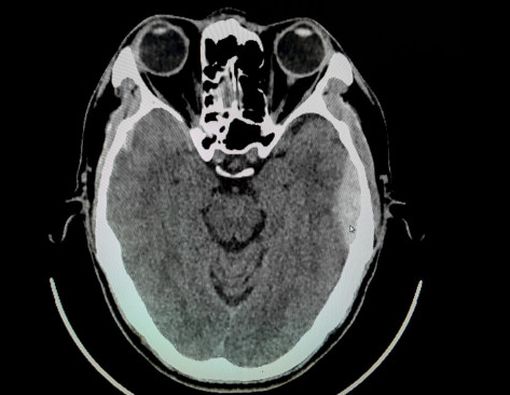

- Pemeriksaan computerized tomography (CT) scan yang dapat menunjukkan adanya massa padat yang mendesak struktur otak menjauh dari tulang tengkorak.